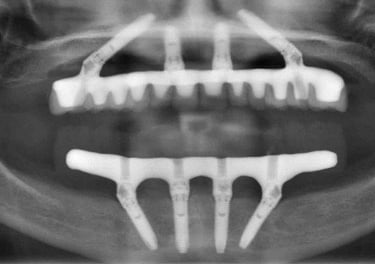

W dniu zabiegu pacjentowi wszczepia się 4 implanty w odpowiednio dobranych miejscach w szczęce i/lub żuchwie. Na implantach już w dniu wykonania zabiegu mocuje się stały most z pełnym uzębieniem w linii uśmiechu. Po pół roku pierwszy (tzw. tymczasowy most) wymieniany jest na most stały wzmocniony specjalną tytanową belką (oczywiście niewidoczną i niewyczuwalną).

Zdjęcia dzięki uprzejmości prof. Paulo Maló. Prezentacja na forum korporacyjnym sponsorowanym przez Nobel Biocare na dorocznym kongresie Europejskiego Stowarzyszenia na rzecz Osseointegracji, Lizbona, 27 września 2019 r.

Chirurg umieszcza 4 tytanowe implanty w kości szczęki i/lub żuchwy w punktach zaplanowanych wcześniej na podstawie tomografii pacjenta.

Tymczasowy most jest przykręcony na stałe już w dniu zabiegu chirurgicznego. Most jest w pełni funkcjonalny i bardzo estetyczny.

Do implantów mocuje się specjalne łączniki, na których potem zamontuje się stały most.